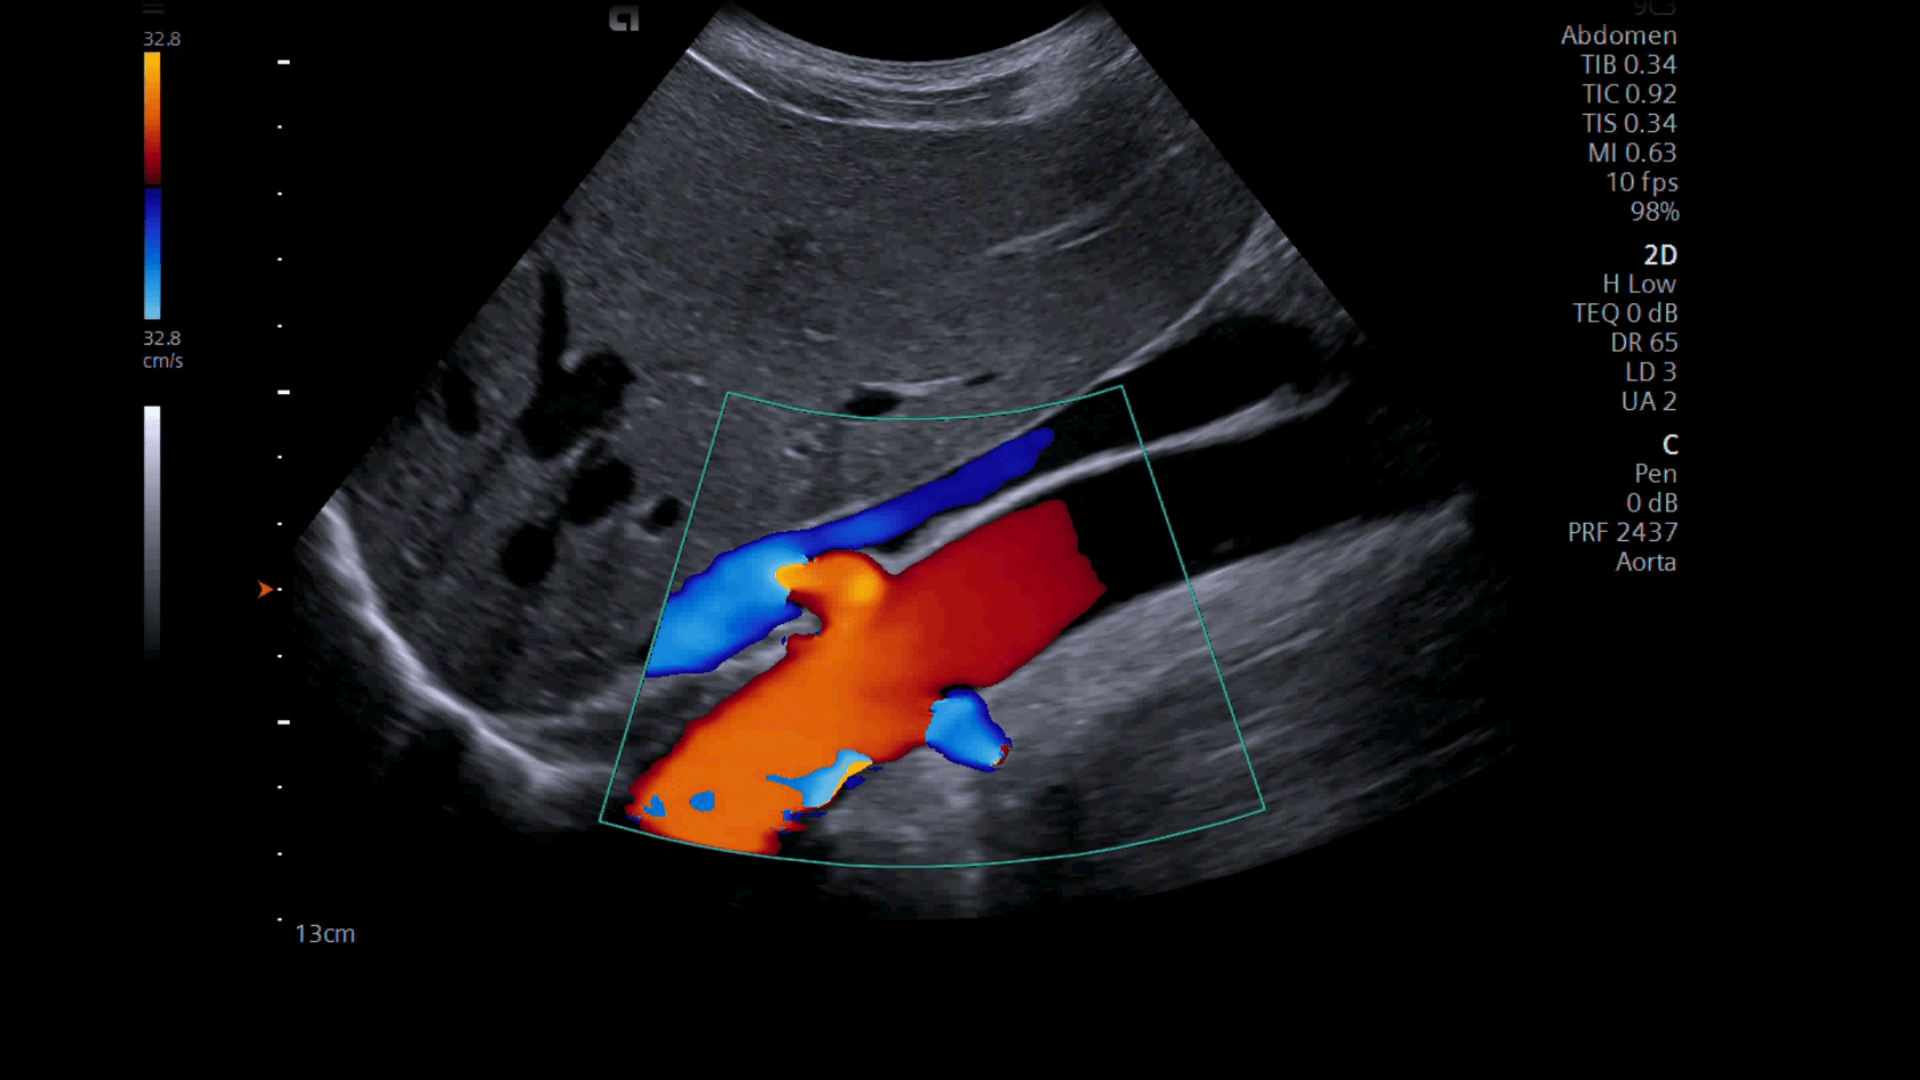

Ultrasound Wallpapers - Wallpaper Cave

wallpapercave.comultrasound hematoma subchorionic hemorrhage pregnancy fetal

wallpapercave.comultrasound hematoma subchorionic hemorrhage pregnancy fetal